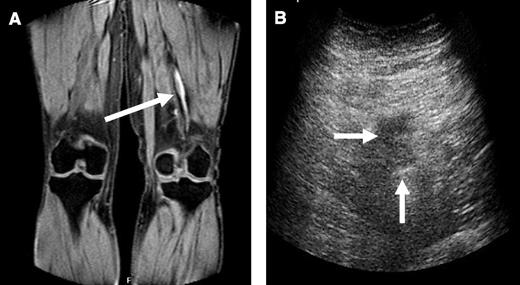

MRDTI was abnormal in 37 of 39 patients of group 1 with symptomatic recurrent ipsilateral DVT. For two patients in this group, the MRDTI images were judged as normal. In the first 57-year-old male patient, recurrent DVT was demonstrated by CUS in a new proximal segment (popliteal vein) when compared with the original ultrasonography of his first DVT in the femoral vein only 10 months earlier (Table 1). The D-dimer level at the moment of suspected recurrence was 1195 ng/mL. The ultrasonography result of the second 18-year-old male patient was judged to be a more propagated thrombotic obstruction of the popliteal vein with new extension into the popliteal segment below the knee when compared with the ultrasonography of the first DVT diagnosed 17 months earlier. His D-dimer level at the most recent presentation of suspected recurrent DVT was 584 ng/mL (Table 1). The onset of symptoms of DVT was less than 48 hours in both patients, and neither reported respiratory or chest symptoms indicative of the presence of acute PE. MRDTI images and corresponding ultrasonography images are displayed in Figure 1 for a patient from study group 1 with acute recurrent ipsilateral DVT.

Abnormal signal on MRDTI in the popliteal vein of the left leg. (A) Arrow indicates positive MRDTI signal in a patient with symptomatic and CUS-proven ipsilateral recurrent DVT in the popliteal vein; (B) arrows indicate incompressibility of corresponding vein on ultrasonography.